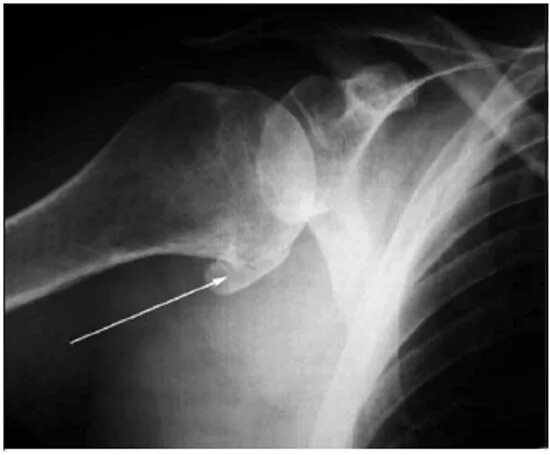

Как лечить артроз плечевого сустава 2 степени